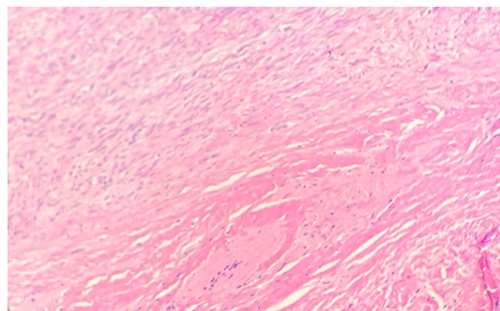

Per gross report, the mass measured 3.5 cm. The mass was biopsied, which showed an infiltrative tumor involving skeletal muscle and composed of large, epithelioid cells with abundant, granular cytoplasm (Fig. 1), indicating the typical features of granular cell tumor. In the central aspect of the mass, a proliferation of monomorphic myofibroblast-like spindle cells in streaming fascicles were found (Fig. 1), also indicating the typical features of desmoid-type fibromatosis. Additionally, the granular cells showed pale basophilic to amphophilic cytoplasm. No pleomorphism was noted. The microscopic examination of the excised mass revealed various morphological tumor cells. Immunohistochemical stains showed that the epithelioid cells are positive for S100 (Fig. 2) and CD68 and negative for pan-cytokeratin. The spindle cells are focally positive for SMA in a myofibroblastic pattern.

Microscopic examination reveals tumor cells are positive for S100. IHC 20X.